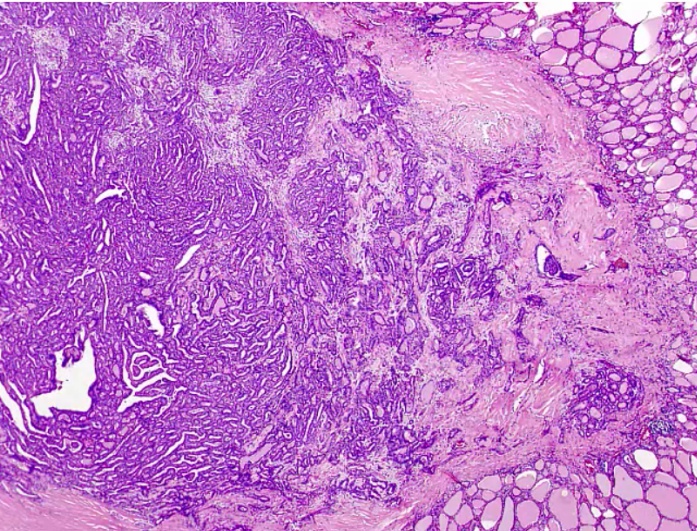

_Occurs when fibrous tissue (collagen) replaces thyroid parenchyma, causing the patient to be hypothyroid.

.,Riedel Thyroiditis. Note how the thyroid gland parenchyma has been overrun by fibrous tissue.

_The thyroid gland is:

Fixed

'Hard as wood' or 'rock-like'

Painless

Often extends beyond the thyroid:

parathyroid gland: hypoparathyroidism

recurrent laryngeal nerves: hoarseness

trachea compression: difficulty breathing.,

_Fibrosis extends beyond the thyroid capsule and into the surrounding tissue in both Riedel thyroiditis and anaplastic carcinoma. A patient with Riedel thyroiditis will be younger (average age 40) than a patient with anaplastic carcinoma, and malignant cells will be absent on biopsy..